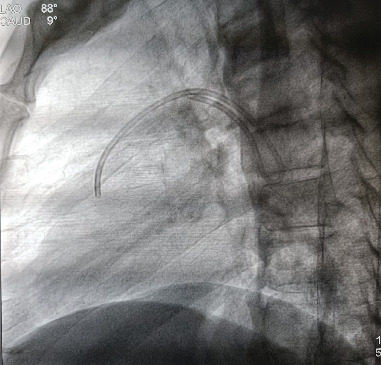

植入式皮下化疗孔是肿瘤化疗的常规载体。自发的导管脱位和导管栓塞是手术中罕见的并发症。在此,我们报告我们的经验,病人表现为自发性脱位和导管迁移到肺动脉。家族性腺瘤性息肉病合并右结肠腺癌患者行全直结肠切除术,经颈内静脉放置化疗孔,进行FOLFOX辅助化疗。被夹住的导管由介入心脏病专家通过经皮回收成功处理。

Implantable subcutaneous chemoports are routinely employed for delivering chemotherapy in oncology. Spontaneous catheter dislodgement and embolization of the catheters are rare complications of the procedure. Herein, we report our experience with a patient presenting with spontaneous dislodgement and migration of the catheter to the pulmonary artery. The patient having familial adenomatous polyposis with adenocarcinoma of the right colon underwent total proctocolectomy and had placement of the chemoport through the internal jugular vein for adjuvant FOLFOX chemotherapy. The entrapped catheter was successfully managed by percutaneous retrieval by an interventional cardiologist.